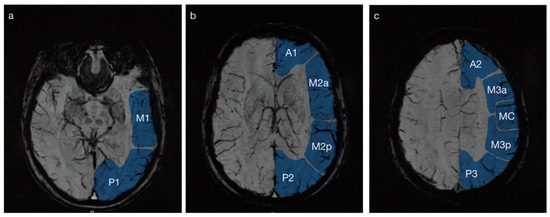

Each MRI scan was evaluated by a board-certified neuroradiologist (NS) at three horizontal levels: at the mesencephalon level, the basal ganglia level and the insula level (Figure 1). The MRI scans were specifically evaluated for SWI changes at a later timepoint than the presentation at the emergency department. A total of 10 regions per hemisphere were defined. The first slice from inferior to superior is based on the level of the mesencephalon and includes the regions P1 (occipital inferior) and M1 (temporal inferior). The second slice at the level of the basal ganglia includes P2 (occipital superior), M2p (temporal superior), M2a (temporal opercular) and A1 (frontal inferior). The last slice parallels the ventricles above the insula and includes P3 (parietal), M3 (frontoparietal excluding MC), MC (motor cortex, central) and A2 (frontal superior).

Figure 1.

Three axial MR SWI slices, arranged from inferior to superior, at the level of (a) the mesencephalon, (b) the basal ganglia and (c) the centrum semiovale just above the lateral ventricles. P1 = occipital inferior, M1 = temporal inferior; P2 = occipital superior, M2p = temporal superior, M2a = temporal opercular, A1 = frontal inferior; P3 = parietal, M3p and M3a = frontoparietal excluding MC (divided into posterior and anterior sections), MC = motor cortex, central, A2 = frontal superior.